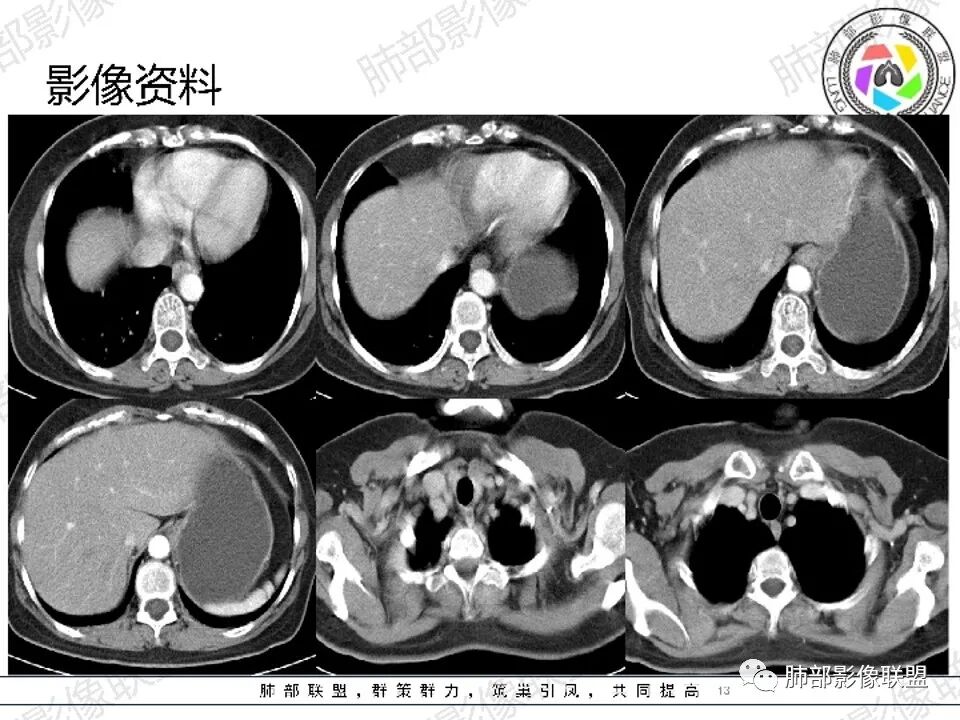

约10%~15%的肺转移发生在进展期结直肠癌,其中大部分是双肺多发转移,只有约2%~7%是孤立性肺转移。消化道脏器的血液回流入门静脉。结、直肠癌的第一转移站为肝,肺为第二转移站,约有10%~20%跳过第一转移站(肝)首先出现肺转移者只有2%~4%,多项研究表明不论是否伴同时性还是异时性肺转移,结直肠癌患者发生肺转移与结直肠癌发生部位相关,一般来说,直肠癌患者发生肺转移的概率比结肠癌患者要大,这与静脉血回流解剖很大关系,原因可能是因为直肠癌细胞由直肠中下静脉直接流向下腔静脉后迅速到达肺脏,从而形成肺转移灶,而结肠癌细胞则由门脉系统流向肝脏易形成肝转移灶。

结直肠癌肺转移瘤多数边缘光整清楚,可以分叶、毛刺、空洞及强化不均匀,有时候与原发肿瘤不易鉴别;结直肠癌肺转移瘤有片状低密度区考虑与结、直肠癌含有粘液及转移性腺癌有更多的坏死成份有关。另结直肠癌中粘液腺癌远处转移灶内部可出现钙化,其病理类型属于黏液样钙化。

直肠癌肺转移瘤中低密度区

1.血道转移,落脚于血管末梢的肺间质,常两肺多发,随机分布,较少造成支气管阻塞,也很少见支气管穿行,罕见出现肺不张或阻塞性肺炎。

4.强化程度不一,取决于原发灶血供特点、病灶内粘液成分多寡及坏死情况等等。